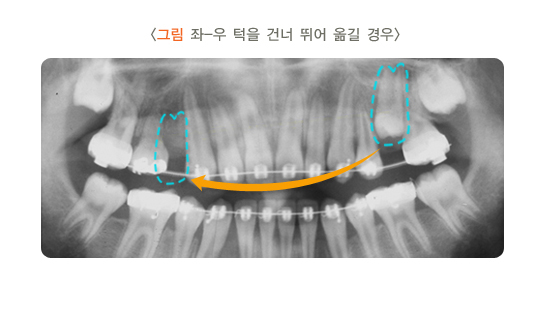

턱교정 수술 전 어느 정도 기간의 교정 치료가 필요한지는 환자의 치열과 골격 상태에 따라 차이가 납니다. 즉, 수술 후 외모 개선이 가장 예쁘고 안정적으로 되게 하려면 치아를 얼마나 움직여야 할지 예상하고 그에 따라 교정 치료 기간을 정합니다. 대개 수술 전에 6개월~1년 이상의 교정 치료를 해서 수술할 때 치아 맞물림이 완벽하게 맞는 것을 목표로 합니다. 요즘은 교정 치료와 수술 기술의 발달로 수술 전의 교정 치료 기간이 많이 단축되고 있습니다. 때에 따라서는 교정 치료가 2~4개월에 끝나기도 합니다.